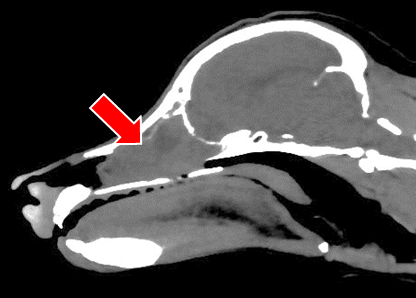

【実施症例】鼻腔内腫瘍に対する動注療法

トイプードル、11歳、雌。

約半年前に放射線治療を受けたが腫瘍が再発。 鼻腔内腫瘍の栄養血管である上顎動脈にマイクロカテーテルで選択的に抗がん剤を注入した。 1ヵ月後のCT検査では腫瘍の1/2以下の縮小が認められた。

頭部のX線透視像

頭部動脈のDSA像

上顎動脈への注入

実施前

実施後